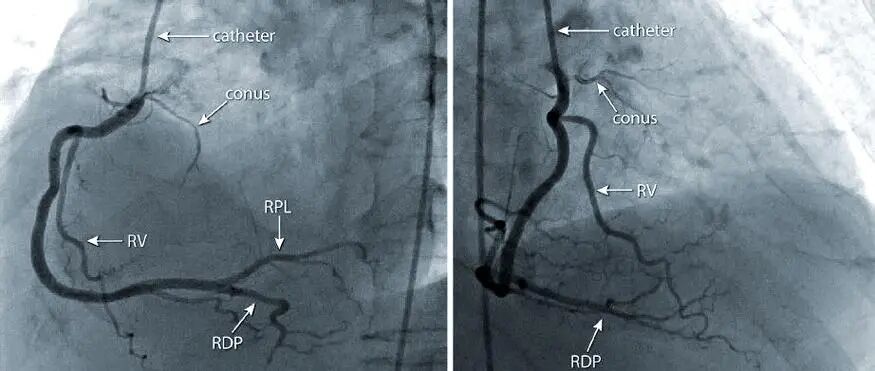

别被“CT”吓到,其实它比很多检查都简单。一个无创、无痛的高分辨率成像技术,能立体还原你冠状动脉的全貌。

做完后,医生可以直观看到血管内有没有斑块,斑块大小、位置、是否钙化,以及有没有引发血管狭窄。

血管狭窄程度:狭窄超过70%的,很大可能需要进一步手术干预。

此外,做过心脏支架或搭桥手术的患者,也可以在我院预约进行支架术后复查, 高端CT的0.17毫米超高分辨率,能清晰显示支架内的情况,精准评估术后血管通畅性。